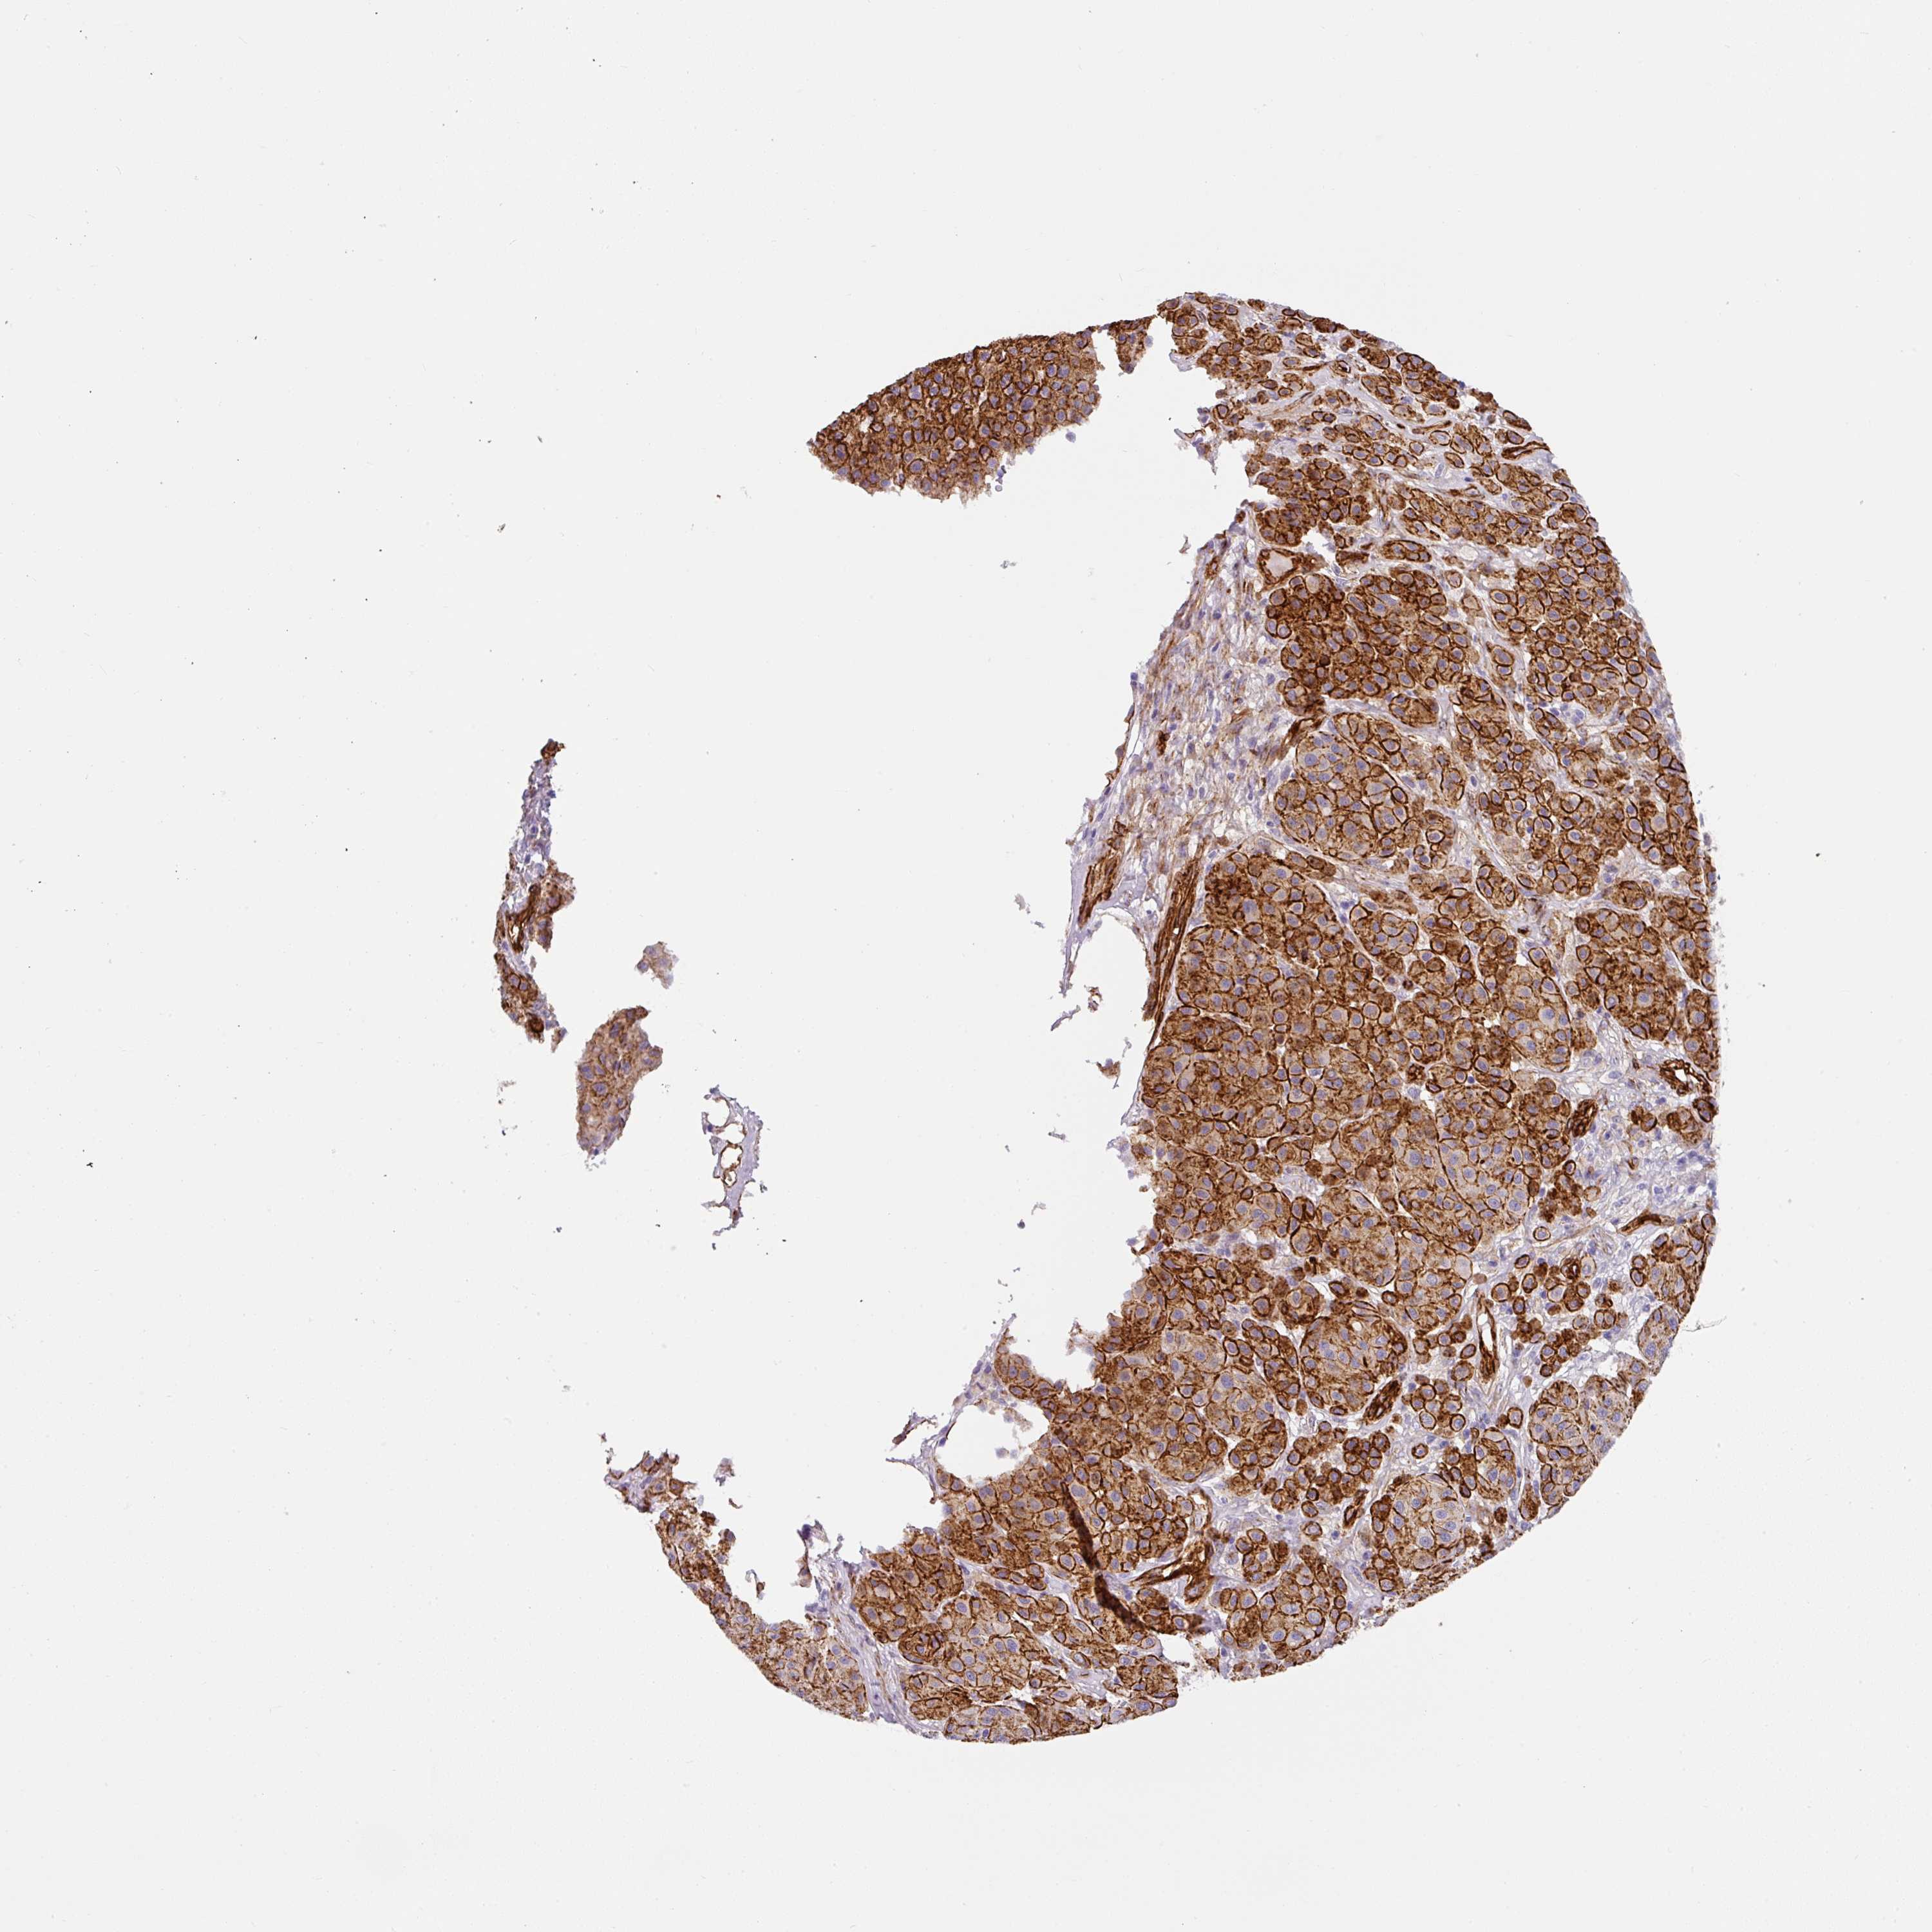

MELANOMA - Protein expressioni

A mouse-over function shows sample information and annotation data. Click on an image to view it in a full screen mode. Samples can be filtered based on level of antibody staining by selecting one or several of the following categories: high, medium, low and not detected. The assay and annotation is described here.

Note that samples used for immunohistochemistry by the Human Protein Atlas do not correspond to samples in the TCGA dataset.

Antibody stainingi

Antibody staining in the annotated cell types in the current human tissue is reported as not detected, low, medium, or high, based on conventional immunohistochemistry profiling in selected tissues. This score is based on the combination of the staining intensity and fraction of stained cells.

Each image is clickable and will lead to virtual microscopy that enables deeper exploration of all samples and also displays staining intensity scores, fraction scores and subcellular localization as well as patient and tissue information for each sample.

Antibody HPA052708

Staining

High

Medium

Low

Not detected

Intensity

Strong

Moderate

Weak

Negative

Quantity

>75%

75%-25%

<25%

None

Location

Nuclear

Cytoplasmic/membranous

Cytoplasmic/membranous,nuclear

Malignant melanoma, NOS

Malignant melanoma, Metastatic site